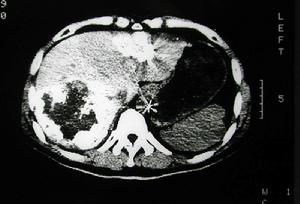

3、血管造影或數字減影血管造影(圖1)它可以提供最為詳盡準確的病情資料,例如病變部位、範圍程度為血管成形手術或手術方式的選擇提供依據。